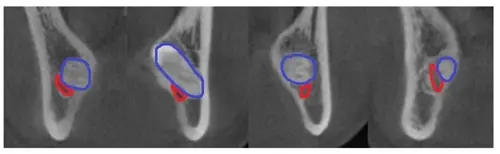

▲ 하악 사랑니 발치 전 CT사진. 사랑니(파랑색)와 하치조신경(붉은색)이 붙어있다.

▲ 하악 사랑니 발치 후 하치조신경(흰색 화살표)이 드러난 환자들.